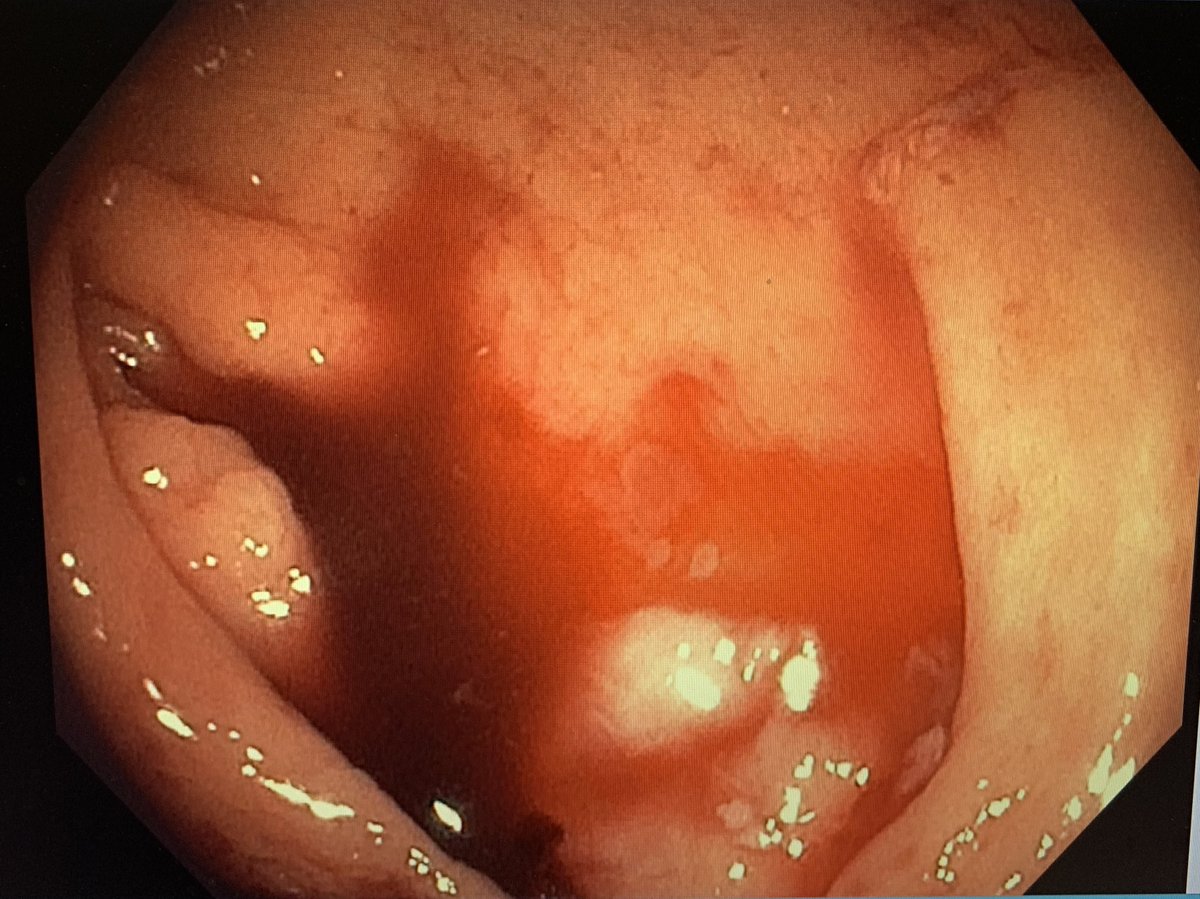

Clear cap tamponade:

Tip #2: Band ligation & OTSC use a cap, which can provide temporary tamponade of active bleeding. This minimizes red out & need for suction. If bleeding varix, first get into stomach, then slowly move up, tamponading varix as you approach it on withdrawal.